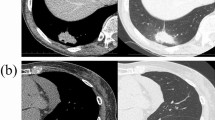

Among MPA cases, 36 patients fell into stage I, 11 into stage II, 6 into stage III, and 2 into stage IV. In LA, 39 (16 solid, 16 acinar, and 7 lepidic) fell into stage I, 12 (10 solid, 1 acinar, and 1 lepidic) into stage II, 8 (4 solid, 1 acinar, and 3 lepidic) into stage III, and 17 (13 solid and 4 lepidic) into stage IV. Seventy-two people had no smoking history, and fifty-nine were smokers, including former smokers and current smokers. The histological images of MPA and LA are presented in Fig. 1.

Immunohistochemical staining and mutation analysis of MPA and LA patients. Three micrometers FFPE sections of MPA (patient 1) and LA (patient 16) were immunostained with hematoxylin and eosin (× 100 magnification). Scale bar 20 μm. Abbreviations: MPA, micropapillary lung adenocarcinoma; LA, lung adenocarcinoma without micropapillary component